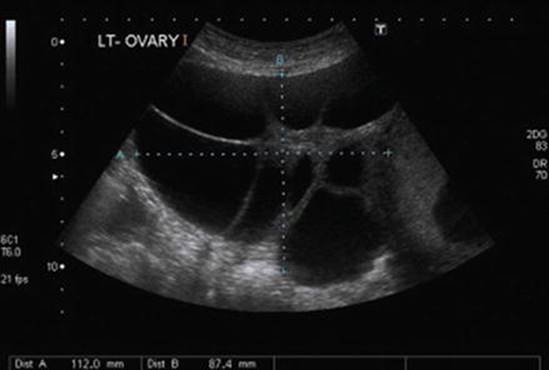

Pelvic ultrasounds in patients with PCOS will reveal multiple peripheral follicles and an overall volume greater than 10 mL (Fig. 4.12); enlargement is usually bilateral, but can be unilateral [68]. The ovarian stroma may also be increased and echogenic, though use of oral contraceptive pills may normalize the appearance of the stroma [69]. Urgent intervention is not indicated, except in cases of suspected torsion; patients can be followed by gynecologists in the outpatient setting for management of oligo-ovulation and hirsutism, as needed.

Fig. 4.12

Polycystic ovarian syndrome. Transvaginal ultrasound of a 21-year-old patient with PCOS reveals several small, peripherally located follicles with a “string of pearls” appearance